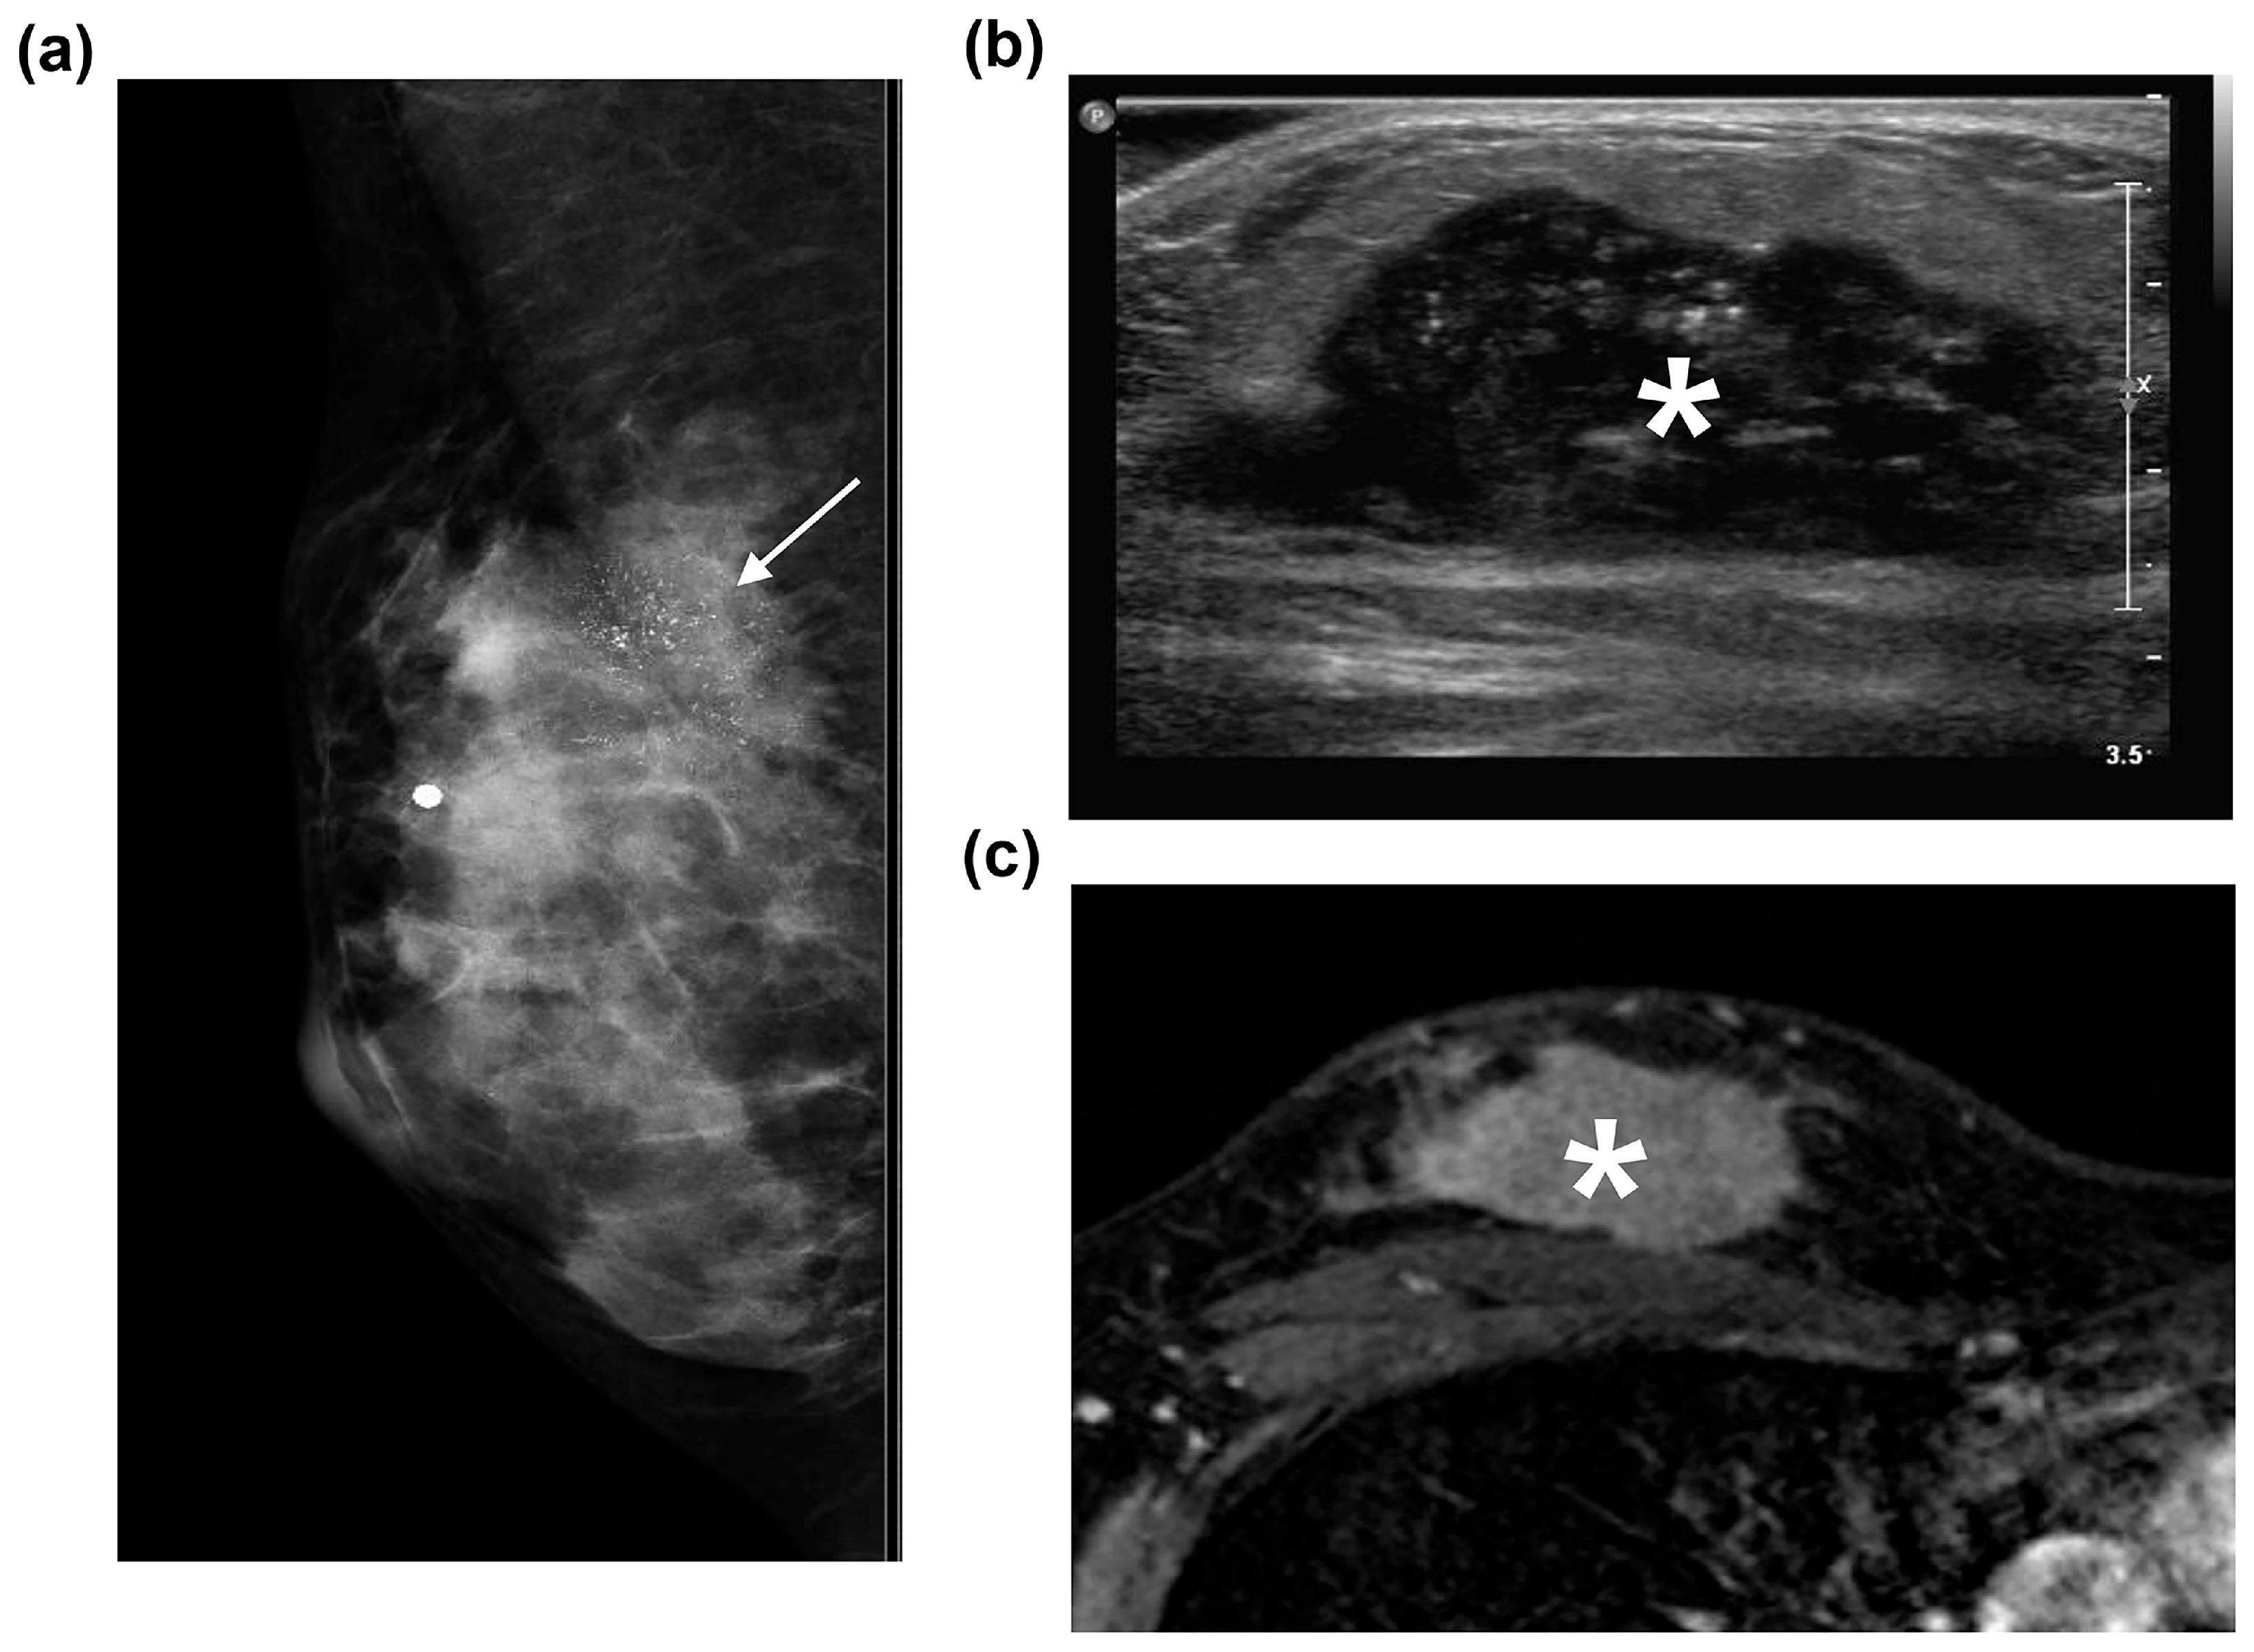

3.2. Radiological Characteristics